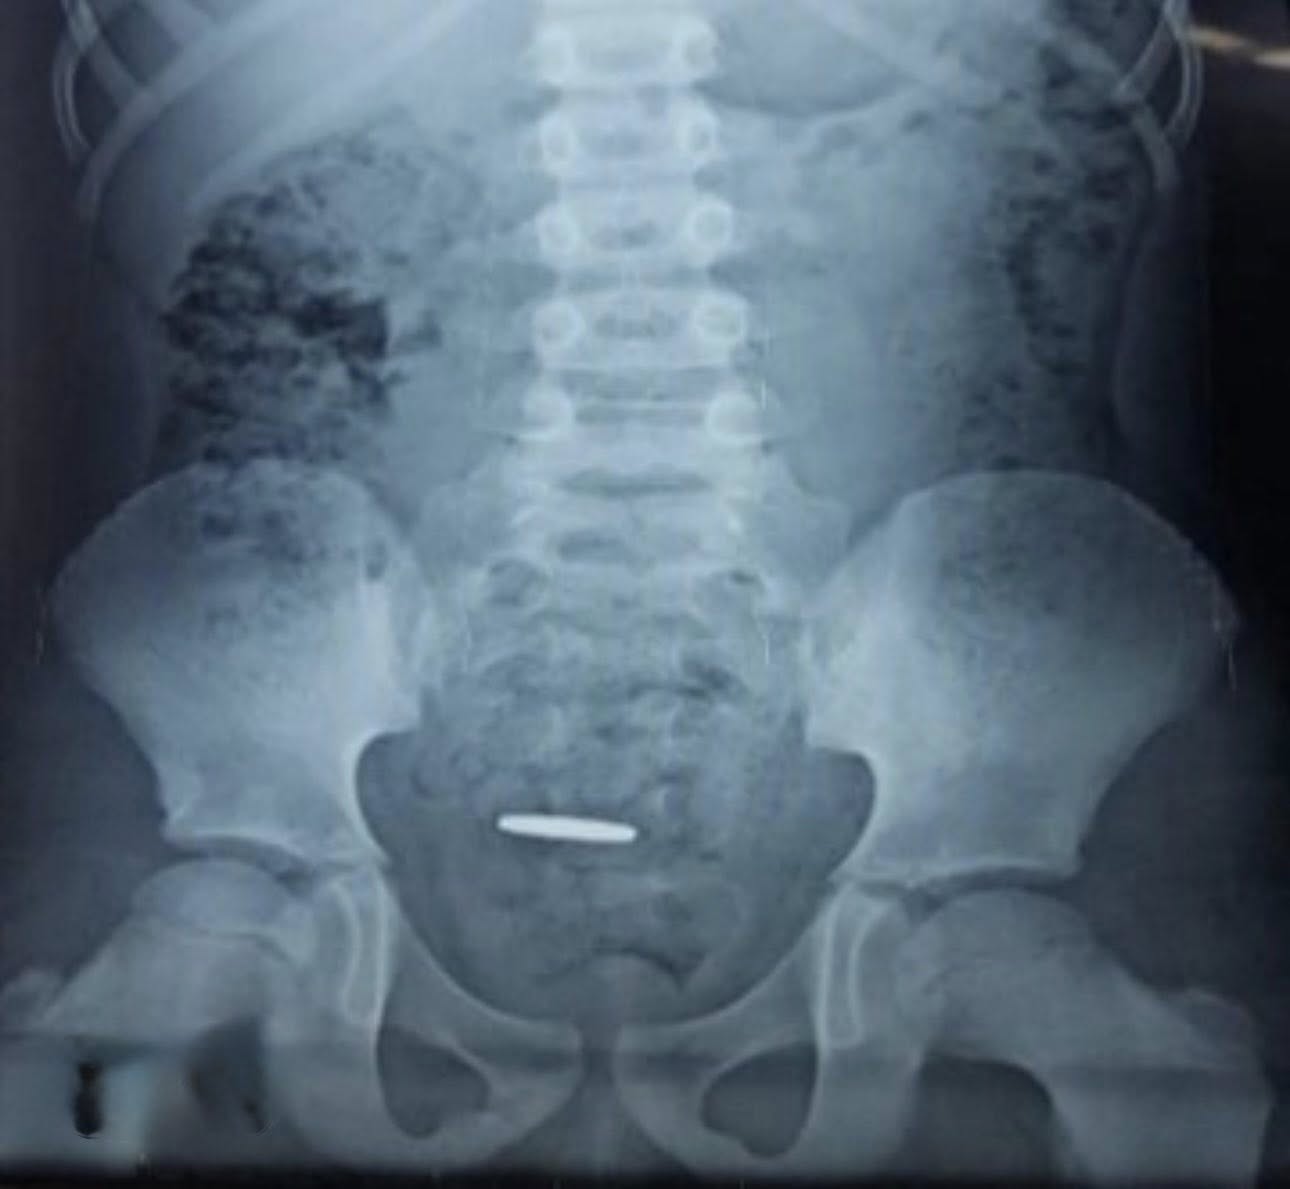

El niño comenzó a sentir malestares. Lo llevaron al médico y le practicaron una radiografía, la cual reveló la presencia del cuerpo extraño en su estómago.